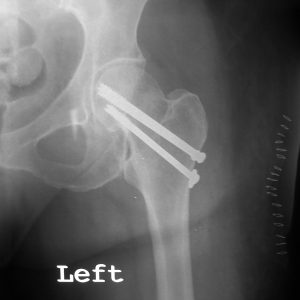

Σχετικά με τα απαρεκτόπιστα κατάγματα του αυχένα του μηριαίου οστού αντιμετωπίζονται κατά κανόνα με κοχλίωση, ενώ τα παρεκτοπισμένα με αρθροπλαστική συνήθως ημιαρθροπλαστική ή ολική αρθροπλαστική ισχίου σε νεότερους και δραστήριους ασθενείς. Τα διατροχαντήρια και υποτροχαντήρια κατάγματα αντιμετωπίζονται με ανοικτή ανάταξη και εσωτερική οστεοσύνθεση, κυρίως με ενδομυελικό ήλο ισχίου ή, σε σταθερές περιπτώσεις, με ολισθαίνοντα κοχλία. Η μη χειρουργική αντιμετώπιση είναι εξαιρετικά περιορισμένη και αφορά μόνο πολύ σταθερά κατάγματα ή ασθενείς με ιδιαίτερα επιβαρυμένο ιατρικό ιστορικό και ελάχιστη προϋπάρχουσα κινητικότητα.